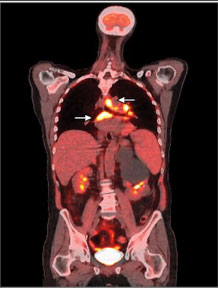

Kontrol toraks BT’sinde yeni gelişen subkarinal, paratrakeal ve hiler lenfadenopati görüldü. Pulmoner nodül ve daha önce görülen opasiteler saptanmadı. Sol üst lobdaki patolojik görüntüler büyük ölçüde düzelmişti. Enfeksiyon olasılığı göz önüne alınarak glukokortikoid tedavisi kesildi ve metastaz şüphesiyle pozitron emisyon tomografisi (PET) çekildi. PET’de supraklavikular ve mediastinal LAP tespit edildi (Resim 5).

Resim 5. PET görüntüsü